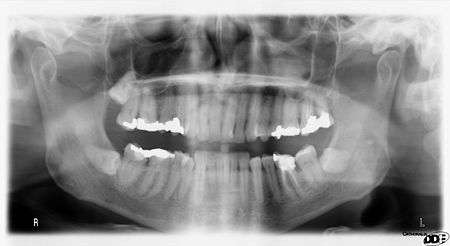

OPTs are used by health care professionals to provide information on:

- Impacted wisdom teeth diagnosis and treatment planning - the most common use is to determine the status of wisdom teeth and trauma to the jaws.

- Periodontal bone loss and periapical involvement.

- Finding the source of dental pain

- Assessment for the placement of dental implants

- Orthodontic assessment. pre and post operative

- Diagnosis of developmental anomalies such as cherubism, cleido cranial dysplasia

- Carcinoma in relation to the jaws

- Temporomandibular joint dysfunctions and ankylosis.

- Diagnosis of osteosarcoma, ameloblastoma, renal osteodystrophy affecting jaws and hypophosphatemia.

- Diagnosis, and pre- and post-surgical assessment of oral and maxillofacial trauma, e.g. dentoalveolar fractures and mandibular fractures.

- Salivary stones (Sialolithiasis).

- Other diagnostic and treatment applications.[1]